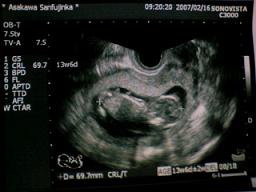

2007年2月16日撮影。

13w4d

頭殿長は69.7oになりました!

赤ちゃんは下向きになっていて、右が頭、左の体の上部に背骨、左端に足が写ってます。

顔のとこにある白いのは、先生に聞かなかったけどおててかな?

指のようなものが写っていて、まるで顔を隠しているようだけど・・・w